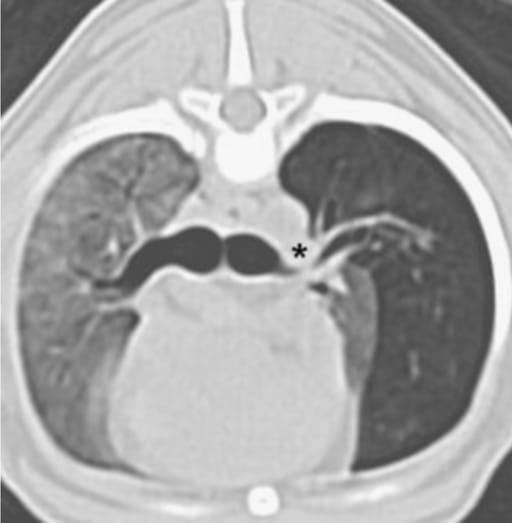

Fig. 4. Postcontrast transverse CT image at the level of T6. Note the hyperlucency of the caudal part of the left cranial lung lobe and focal nar- rowing of the bronchus to that lobe. A pulmonary artery is located just dorsal to the narrowed bronchus (asterisk).

Radiographs and CT identified severe hyperinflation and hypoattenuation of the caudal part of the left cranial lung lobe, with mediastinal shift and reduced vascular markings. CT revealed bronchial narrowing without evidence of extrinsic compression or torsion. Histology confirmed bronchial cartilage hypoplasia and overdistended alveoli. The diffuse pulmonary pattern was attributed to noncardiogenic edema. Postoperatively, radiographic signs of pulmonary opacity resolved, and the dog returned to normal health five months after surgery.